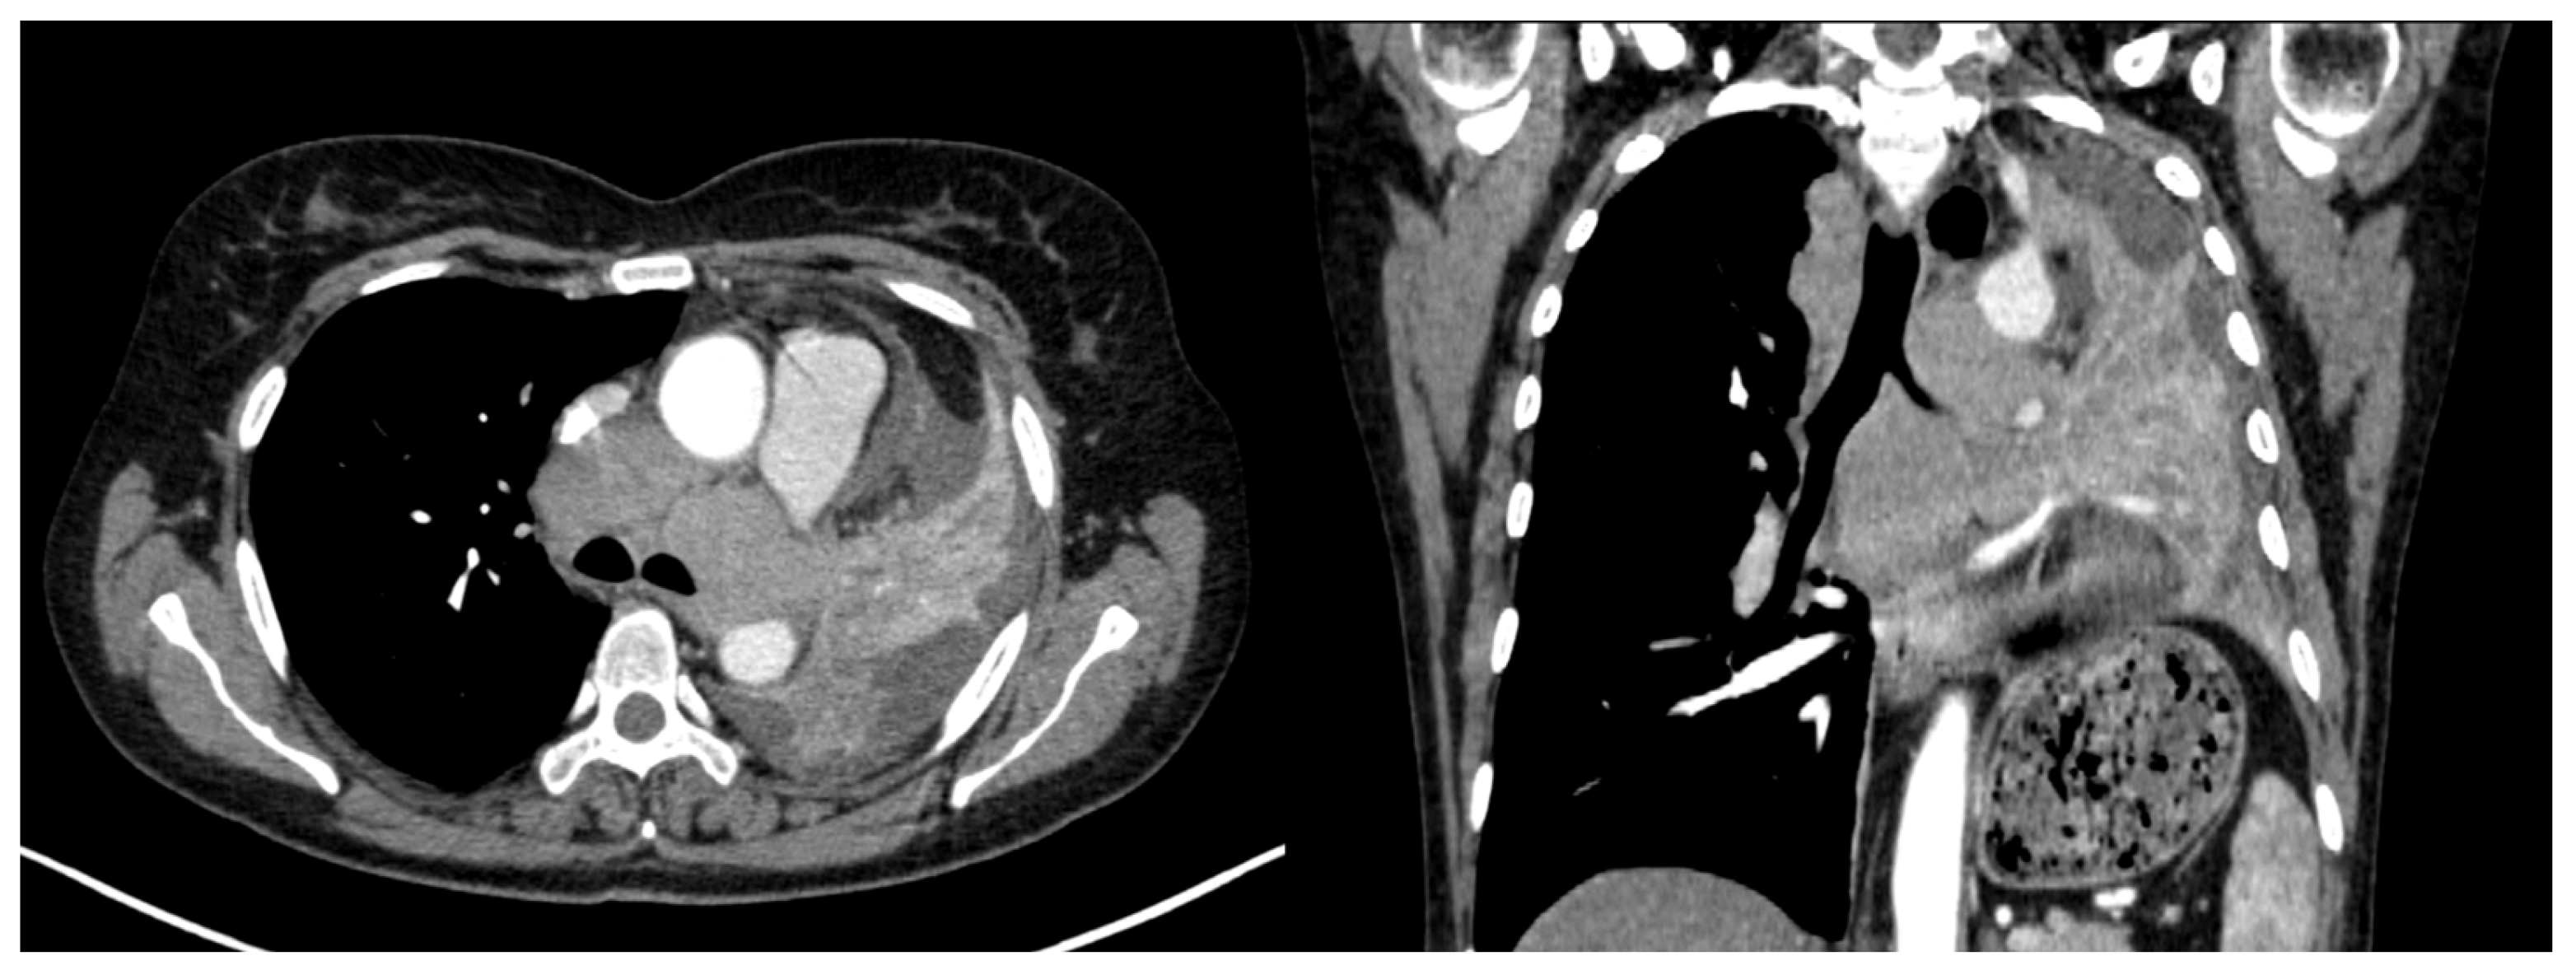

3.2.5. Local Invasion

3.2.7. Lymph Node Involvement